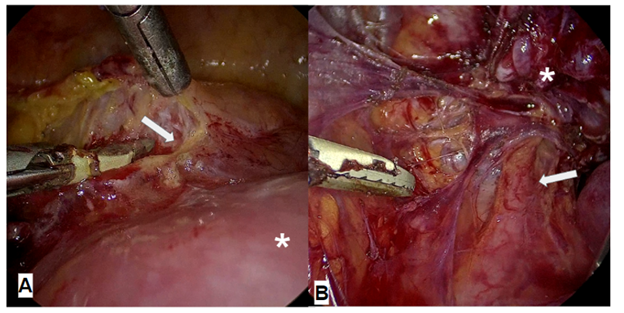

While waiting for the transoperative report, the surgical plan was continued, finding thickened parametrium, bladder extremely adhered to the anterior uterine wall without success in the bladder descent, fixed ureters, so ureterolysis was performed (Figure 2), lesions at the level of the omentum and indurated nodes with enlargement at the level of the left parametrium (Figure 3). At that time, the gynecologic oncology service was consulted and a biopsy of the macroscopic lesions was indicated, a cervical biopsy was taken vaginally, hysteroscopy with endometrial biopsy and cystoscopy with bladder biopsy (Figure 4).

Figure 2 (A) Laproscopic image of the bladder (arrow) attached to the uterine body (asterisk), (B) Laproscopic image of fixed left ureter (arrow).